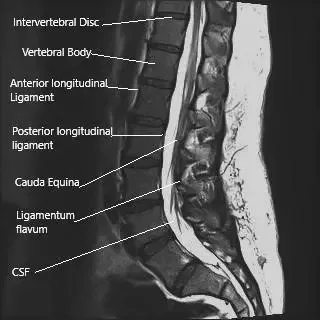

Resonancia magnética de la columna lumbosacra en la sección sagital.

La médula espinal termina al nivel de las vértebras inferiores L1/L2. La médula espinal continúa hacia abajo como un conjunto de raíces nerviosas espinales que se ramifican desde sus respectivos forames neurales. La médula espinal y el conjunto de nervios espinales (cauda equina) están cubiertos por una cubierta protectora conocida como duramadre.

Las inyecciones epidurales de corticosteroides están dirigidas a administrarse justo fuera de la duramadre (espacio epidural). El espacio epidural contiene las raíces nerviosas que salen, el saco dural, los vasos sanguíneos y la grasa. Las inyecciones epidurales de corticosteroides proporcionan una concentración localizada de esteroides.